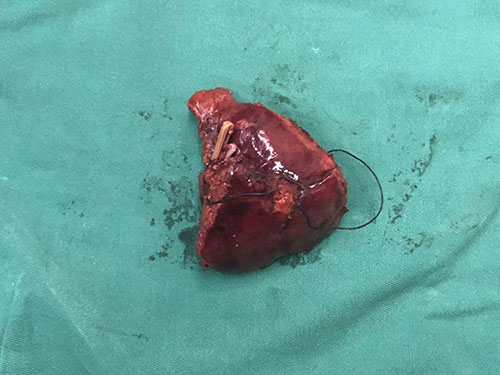

S5 肝癌--腹腔镜S5切除